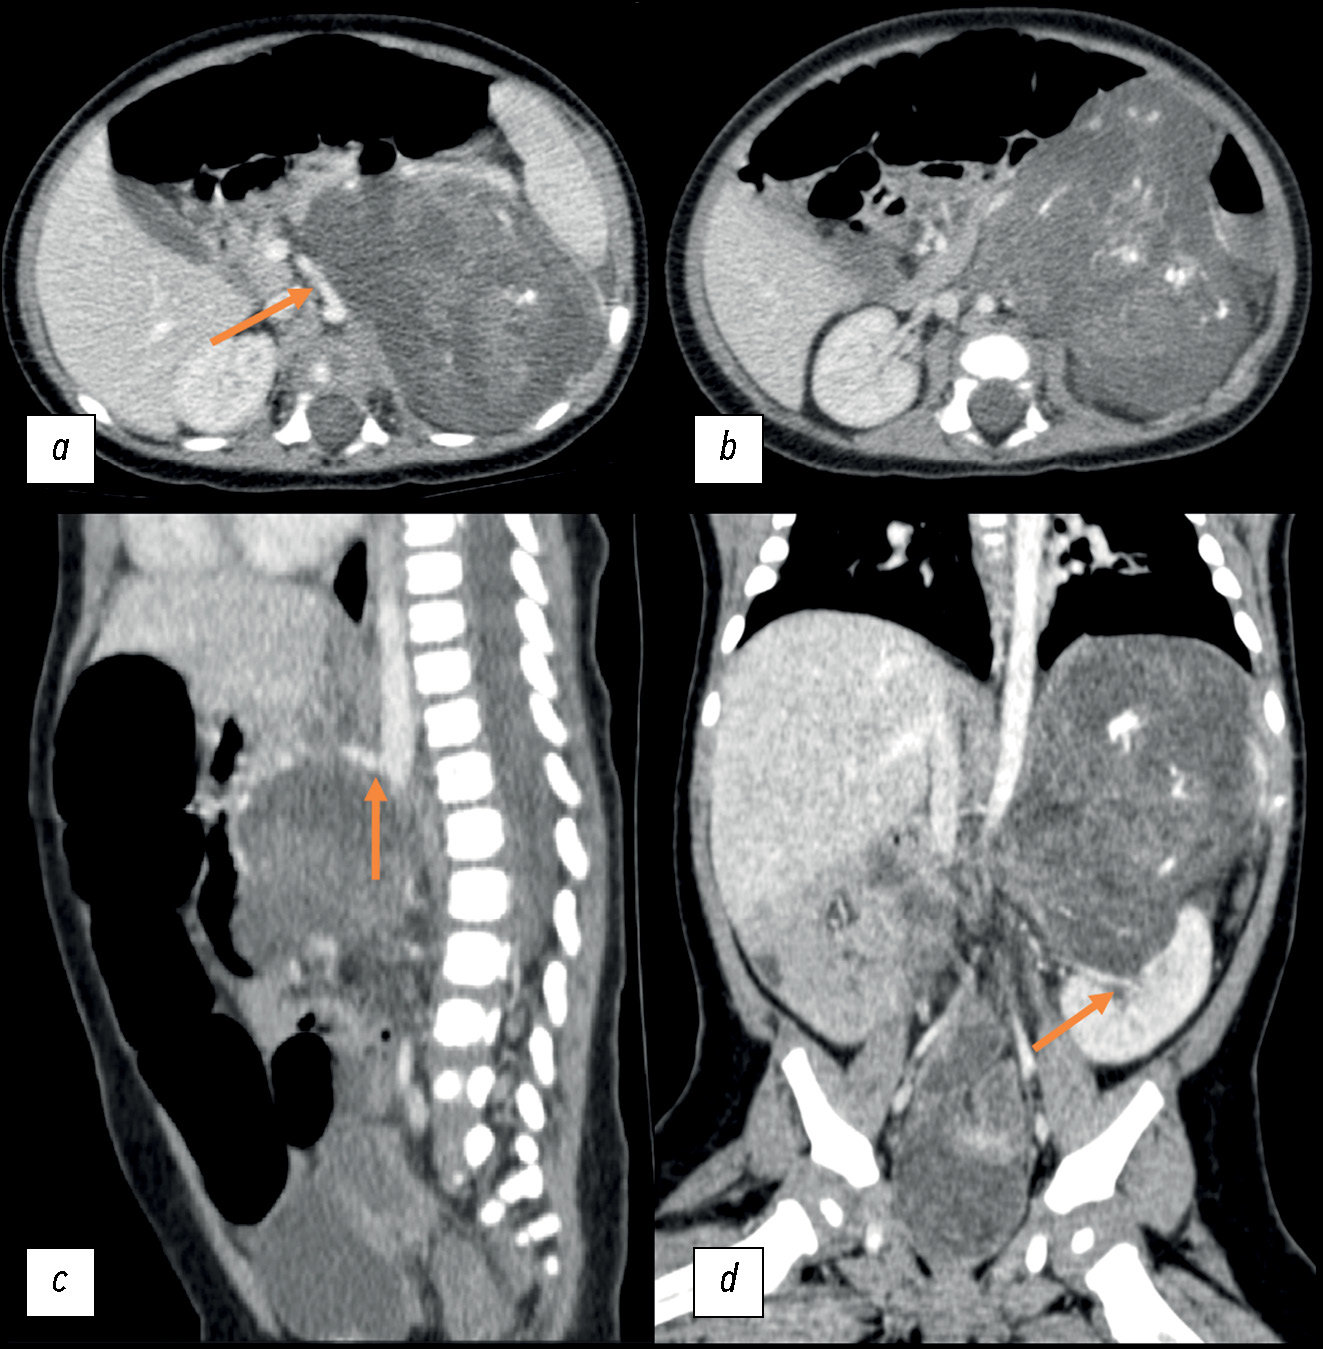

Adult intussusceptions are a rare cause of abdominal obstruction and are usually associated with a neoplastic disease; idiopathic forms are extremely rare. We report a case of enterocolic intussusception in a young woman who experienced symptoms of abdominal obstruction. Imaging findings were reported. On histological examination, no underlying diseases were found. The patient presented at the hospital for computed tomography because of persistent abdominal pain. Computed tomography revealed an enterocolic invagination involving the ileocecal valve and cecum and widespread edematous thickening of the colonic parietal walls.

Idiopathic enterocolic intussusception is an uncommon abdominal urgency in adults. Symptoms can be vague and persistent, delaying an accurate diagnosis. Imaging is crucial in these circumstances to make a diagnosis. Some computed tomography findings, such as a target-like bulk, may be suggestive.